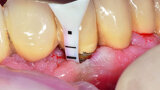

Fig. 1b: Implant in position #14 affected by peri-implantitis: periimplant probing a) with the prosthetic crown in situ and b) after prosthetic crown removal.